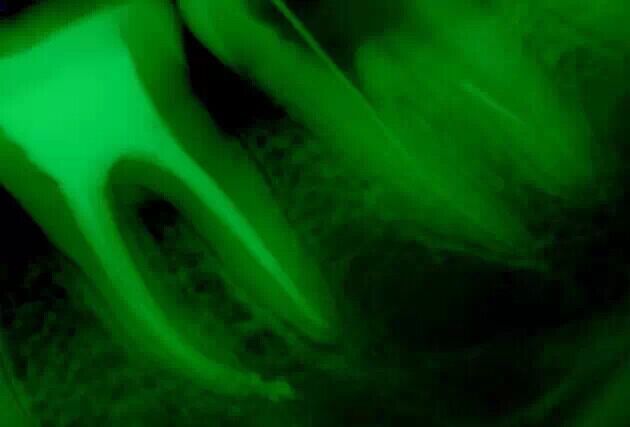

取出斷針時(shí)的X片